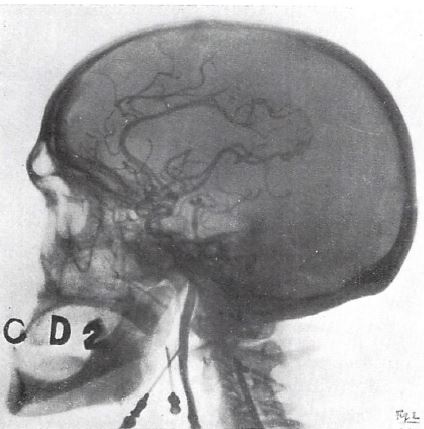

内頸動脈造影(1927)

臨床応用につながる初の本格的な血管造影は,1927年にポルトガルのMonizが報告した脳血管造影である.躯幹部の血管造影も行なわれていなかった当時,いきなり脳血管造影というのはなんとも大胆であるが,Monizは神経科医で,危険かつ不確実な気脳写に替わる診断法として脳血管造影を試みたものである.Monizはその後,統合失調症の治療法としてLobotomy手術を開発し,その功績に対してノーベル生理学医学賞を受賞している.

冒頭では,造影検査の臨床的有用性の例として,やや唐突に当時開発されたばかりの胆嚢造影の話から始まり,続いて脳室造影(気脳写)の現状と問題点を論じて,脳血管撮影の必要性を説いている.造影剤は当初は臭化ストロンチウム(SrBr2),その後ヨウ化ナトリウム(NaI)を使用,前半は頸部の経皮的穿刺,最終的には外科的に内頸動脈を露出して穿刺している.9例の報告のうち,死亡1例,ほとんどに(著者は重篤ではないと言っているが)けっこう重篤な副作用があり,ようやく最後の1例で診断に値する画像が得られている.現在であれば倫理的にも医学的にも到底許されない実験的な論文であるが,ともかく「脳血管造影は可能である」 という結論に達している.